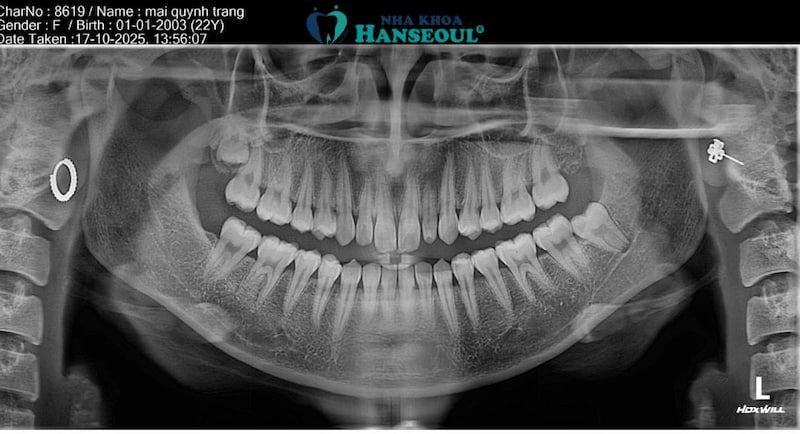

Khách hàng có 2 răng khôn mọc lệch, mọc ngầm ở hàm trên và hàm dưới.

Kết quả thăm khám và phim chụp X-quang cho thấy răng khôn của Trang không chỉ mọc lệch mà còn mọc ngầm độ 3.1 – thân răng nghiêng nhiều về phía trước, chen sát vào răng số 7 và bị kẹt một phần dưới lợi. Với tình trạng này, nếu không xử lý sớm, nguy cơ sâu răng kế cận, viêm quanh răng khôn hoặc đau kéo dài là rất cao. Sau khi được bác sĩ giải thích rõ về tình trạng và phương án điều trị, Trang quyết định nhổ ngay trong buổi hẹn để tránh biến chứng về sau.